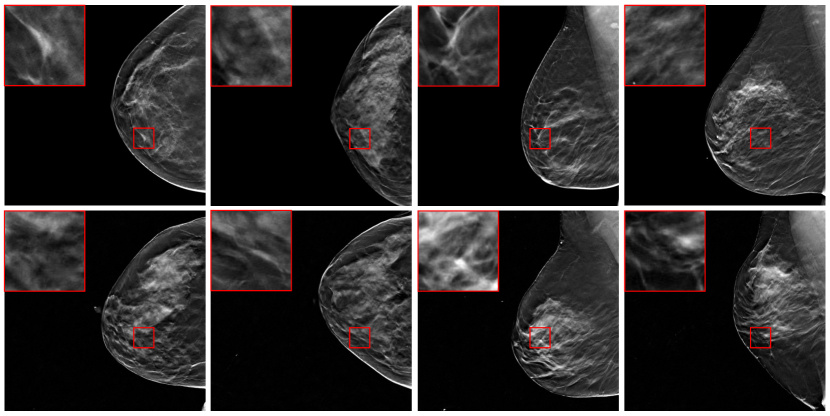

The ADDGAN was compared to the Denoising Diffusion Probabilistic Model (DDPM) [14] and the DDGAN that were directly trained on noisy image data. In addition to these two methods, we also compared ADDGAN to two state-of-the-art AmbientGAN-based methods: Ambient StyleGAN3 [9], which leverages the StyleGAN3 architecture [20], and progressive growing AmbientGAN (ProAmGAN) [9]. Fig. 2 and 3 present examples of the full objects and zoomed-in regions produced by different models for CT and DBT, respectively. The generated images from DDPM and DDGAN are strongly affected by measurement noise. Although Ambient StyleGAN3 and ProAmGAN produced clean images, the generated image textures are significantly distorted.

Refer to caption

Figure 3: The first row shows full DBT images, while the second row are detailed texture in the red-box region. From left to right are (a) ground-truth images, (b) Denoisng-Diffusion-GAN-produced images, (c) Ambient StyleGAN3-produced images, (d) Proposed ADDGAN-produced images.

Examples of ADDGAN-produced DBT images are compared to the ground-truth DBT images in Fig. 4. ADDGAN-produced DBT images have similar visual appearance with the ground-truth DBT images and possess realistic textures.